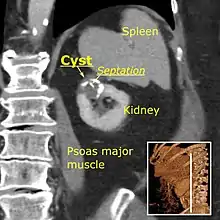

Bosniak II cyst at the lower pole of right kidney with septations within.